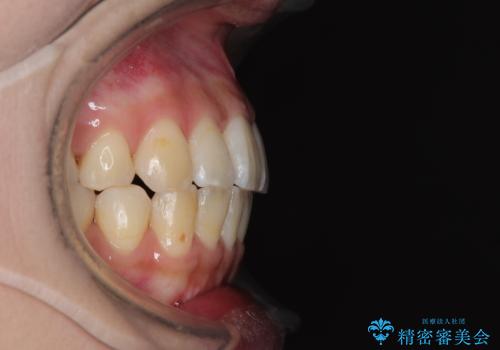

上顎歯列が下顎の歯列に対して狭小であり、一部下顎の奥歯が上顎よりも外側に位置している状態でした。

上顎の急速拡大装置を使用して上顎骨を側方に拡大することで上顎歯列を拡大し、下顎歯列も拡大できるようにすることで、歯列を整えることとしました。

上顎の拡大は、左右どちらに拡大していくのか予想が困難ですが、こちらの患者様では結果として上下正中が一致する方向に拡大され、非常にきれいな仕上がりとなりました。